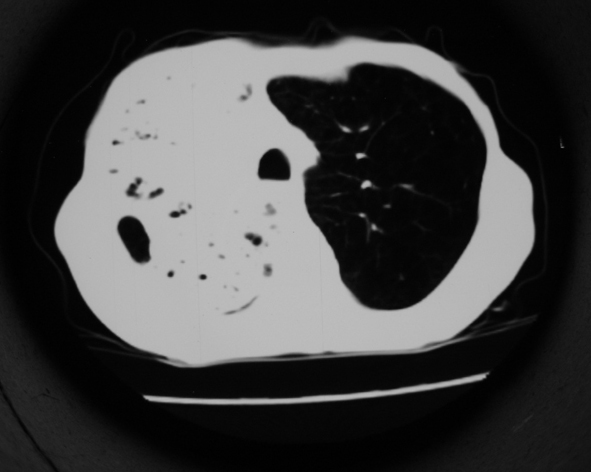

男53岁,咳嗽气短,以往身体健康.

右肺上叶多发多形态空洞及增殖灶,可见团块钙化,胸膜肥厚、粘连,考虑继发型肺结核可能性大

1.右肺上叶干酪性肺炎,2。肺气肿,肺大泡

支持右上肺继发性肺结核并干酪性肺炎,右肺大泡,左肺代偿性气肿。